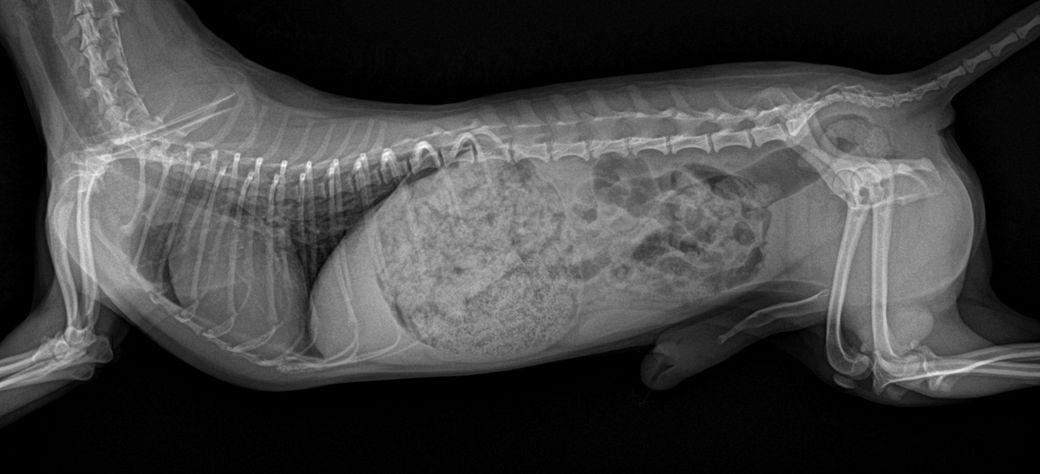

담당 의사선생님께서 십자인대의 문제는 확인이 어렵다고 하셨는데, 보통 X-ray로 확인하지 않나요..?ㅠㅠ 그래서 아하에 계시는 수의사 분들께 병원에서 받아온 X-ray 사진과 병원에 진료 후 내려놨을 때 걷는 영상을 첨부하오니, 100%가아니더라도 십자 인대 수술이 필요해보이는지, 다른 소견은 없는지 등의 진단을 부탁드립니다..!ㅠㅠ

30cm가 이니라 10여도 터질 십자인대는 터집니다. 다만 첨부한 사진에서 양쪽 뒷다리의 측면 사진이 모두 첨부되어야 관절낭을 중심으로 비교 평가할 수 있는데 사진이 누락되어 판단할 수 없습니다. 다만 주관적으로 2번째 첨부 사진에서 아킬레스건의 부종 양상이 관찰되고 슬개골 관절낭의 심한 종창은 보이지 않아 십자인대 단열보다는 아킬레스건 부분단열을 먼저 고려해야 할것으로 보입니다. 주치의의 지시에 따라 평가 진행해도 크게 무방합니다.